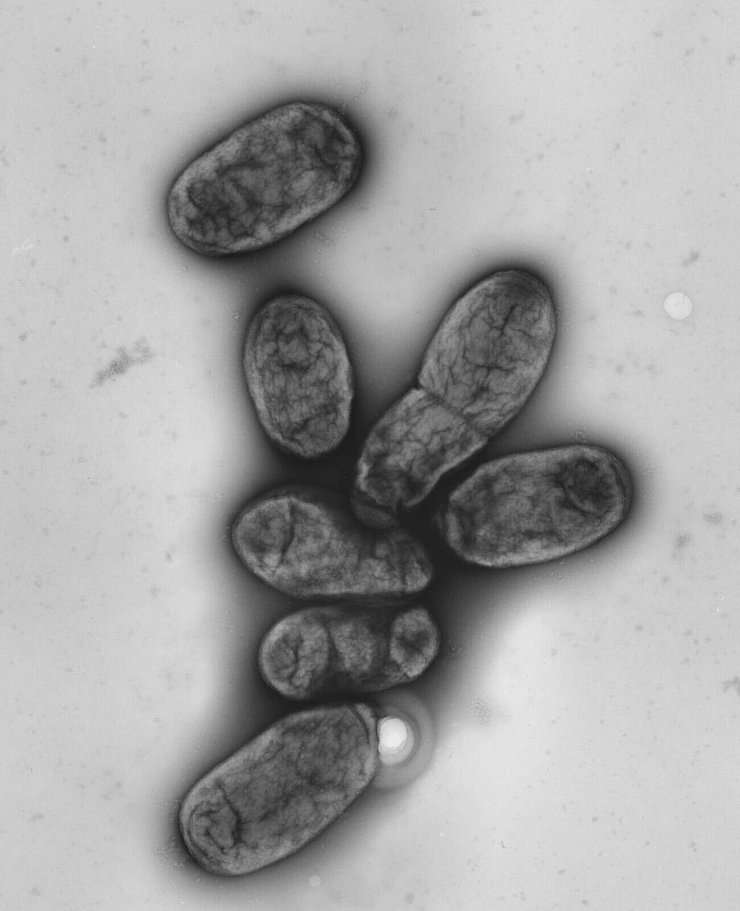

Das Pestbakterium Yersinia pestis - © picture alliance / dpa

Das Pestbakterium Yersinia pestis (© picture alliance / dpa)

Der Pesterreger - das Bakterium Yersinia pestis - sei in vielen Teilen Kaliforniens präsent, so die Behörden. Übertragen werde der Erreger oft durch Bisse von infizierten Flöhen, die sich wiederum bei Eichhörnchen, Streifenhörnchen oder anderen wilden Nagetieren infiziert haben. Daher sei es auf Spaziergängen, Wanderungen oder beim Zelten in der Natur wichtig, Schutzmaßnahmen für Menschen und Haustiere zu ergreifen.